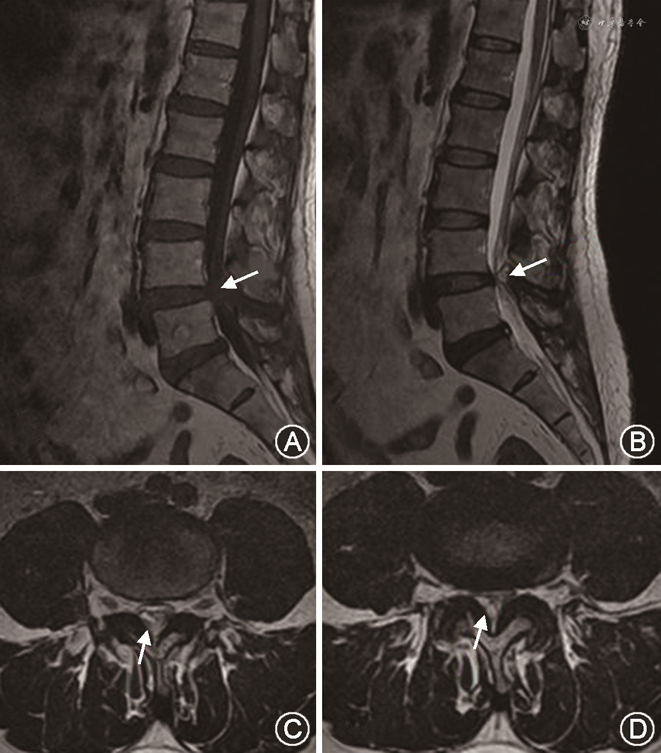

患者男,54岁,以“右下肢麻木、无力2周”为主诉于2021年8月10日入院。患者于2周前无明显诱因出现右下肢疼痛、麻木,以小腿外侧、足背为主,伴右侧足趾背伸无力。查体:双下肢感觉无明显异常,右侧股二头肌、股四头肌、小腿三头肌肌力4级,右侧足拇背伸肌肌力1级,右侧直腿抬高试验50°阳性。腰椎MRI检查显示L4/5椎间隙水平硬脊膜外黄韧带区域类圆形囊性肿物影,边界清楚,位于马尾神经右背外侧,马尾神经明显受压,MRI Tl加权像低信号,T2加权像高信号(图1)。腰椎X线检查提示:腰4椎体向前轻度滑脱、不稳(图2)。诊断“腰椎黄韧带囊肿、腰椎不稳、右侧足下垂”,于全身麻醉下行腰椎后路黄韧带囊肿切除减压融合内固定术,术中在切除病变水平椎板后发现此处黄韧带增厚明显,可见囊肿样病变组织位于黄韧带内,被黄韧带包裹(图3),探查神经根张力较高,进一步行脊柱短缩轴向减压融合内固定术(于L4、L5分别植入一枚合适长度椎弓根螺钉,咬出L4/5棘间韧带及部分骨质,凿除L4下关节突及L5上关节突大部分,扩大L4/5椎间孔,切开L4/5间隙后方纤维环,清除椎间盘组织,连接棒连接双侧螺钉并螺帽固定,椎间隙依次加压,然后锁紧螺帽,图4)。术后病理检查示:镜下见退变变性纤维组织增生,周围血管扩张充血,伴大量浆细胞浸润。病理学诊断为黄韧带囊肿(图5)。术后患者右下肢疼痛、麻木明显缓解,右侧足拇背伸肌肌力3级,随访3个月,症状完全消失,无腰腿痛及下肢麻木等不适,右侧足拇背伸肌肌力4+级。

黄韧带囊肿的临床表现主要与囊肿的位置、大小、生长速率有关,出现神经功能缺失者较为少见,出现急性运动障碍者更为罕见。MRI主要表现为椎管内硬膜外囊性肿物影,被黄韧带完全包裹,边界清楚,T1信号变异较大,T2呈高信号,增强可见肿物轻度强化。SSC的自然病程尚不完全清楚,腰椎关节突囊肿自发吸收的病例鲜有报道,可能与囊肿自发破裂及脊柱自我稳定重建有关[5],目前尚缺少黄韧带囊肿自发吸收的临床报道。SSC的治疗包括手术治疗与非手术治疗。非手术治疗包括局部制动、药物对症支持治疗及CT引导穿刺治疗,主要用于没有神经症状的患者[5]。对于保守治疗失败、经皮穿刺失败、合并神经症状者多建议手术干预,开放或通道辅助下囊肿切除是首选的治疗方式,是否行脊椎融合术存在较大的争议。Lyons等[6]报道了194例SSC患者,18例初次手术时行融合治疗,末次随访时4例患者因滑脱加重进行了二期融合手术。Epstein[7]报道了80例单纯减压术治疗腰椎关节突囊肿患者,11例患者出现滑脱加重/新发滑脱。Wildi等[8]应用单纯的囊肿切除术治疗33例患者,术后1年2例患者因囊肿复发行二次手术。因此,脊椎不稳加重和囊肿复发是影响长期疗效及二次翻修的主要原因[7, 8]。